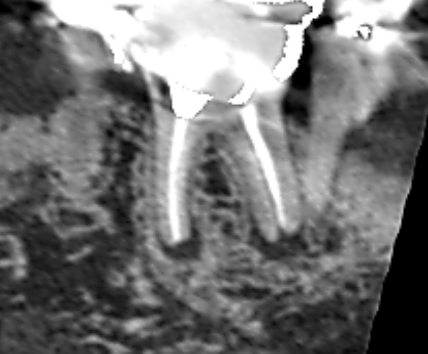

Vol.29 根の先と根の分岐部の両方に膿がみられたケース

- パーフォレーションリペア・ 上顎第一大臼歯・ 低侵襲歯科治療・ 再根管治療・ 根分岐部病変

上顎第一大臼歯の根の先と根の分岐部の両方に膿がみられたケースです。他の歯の根管治療でCTを撮影し…

上顎第一大臼歯の近心根に膿がみられました。実は、Vol.37、Vol.38、Vol.39は同じ患者さ…